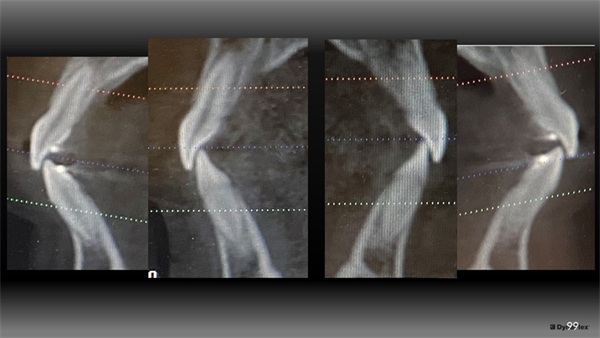

Figure 7 shows final records as treatment finished in 24 months. Notice in Figures 8 and 9 that the upper incisors rolled forward to a more ideal labiolingual inclination during this treatment.

Figure 12 shows that the lower incisors also rolled forward within her thick alveolar housing to couple with this more forward position of her maxillary incisors (pre-tx on the inside, post-tx on the outside). If she had a thinner type of housing, it might have impacted my tolerance for this movement.

The Architects of the Lips: Part 4

Fig. 12

There are obviously many ways to treat this case and I don’t present my way as the best or only way to treat Rylee. Her orthodontic treatment could have been done well without advancing her upper incisors or even by way of extracting permanent teeth. Treatment goals set the course and those vary greatly. For me, it started by looking outside-in and appreciating her lips and what was possible to enhance their presentation, noticing a deficiency in the aesthetic A-P projection of her upper incisors in her smile, and then visualizing her mandibular housing via CBCT to assess how this occlusal change might be tolerated.